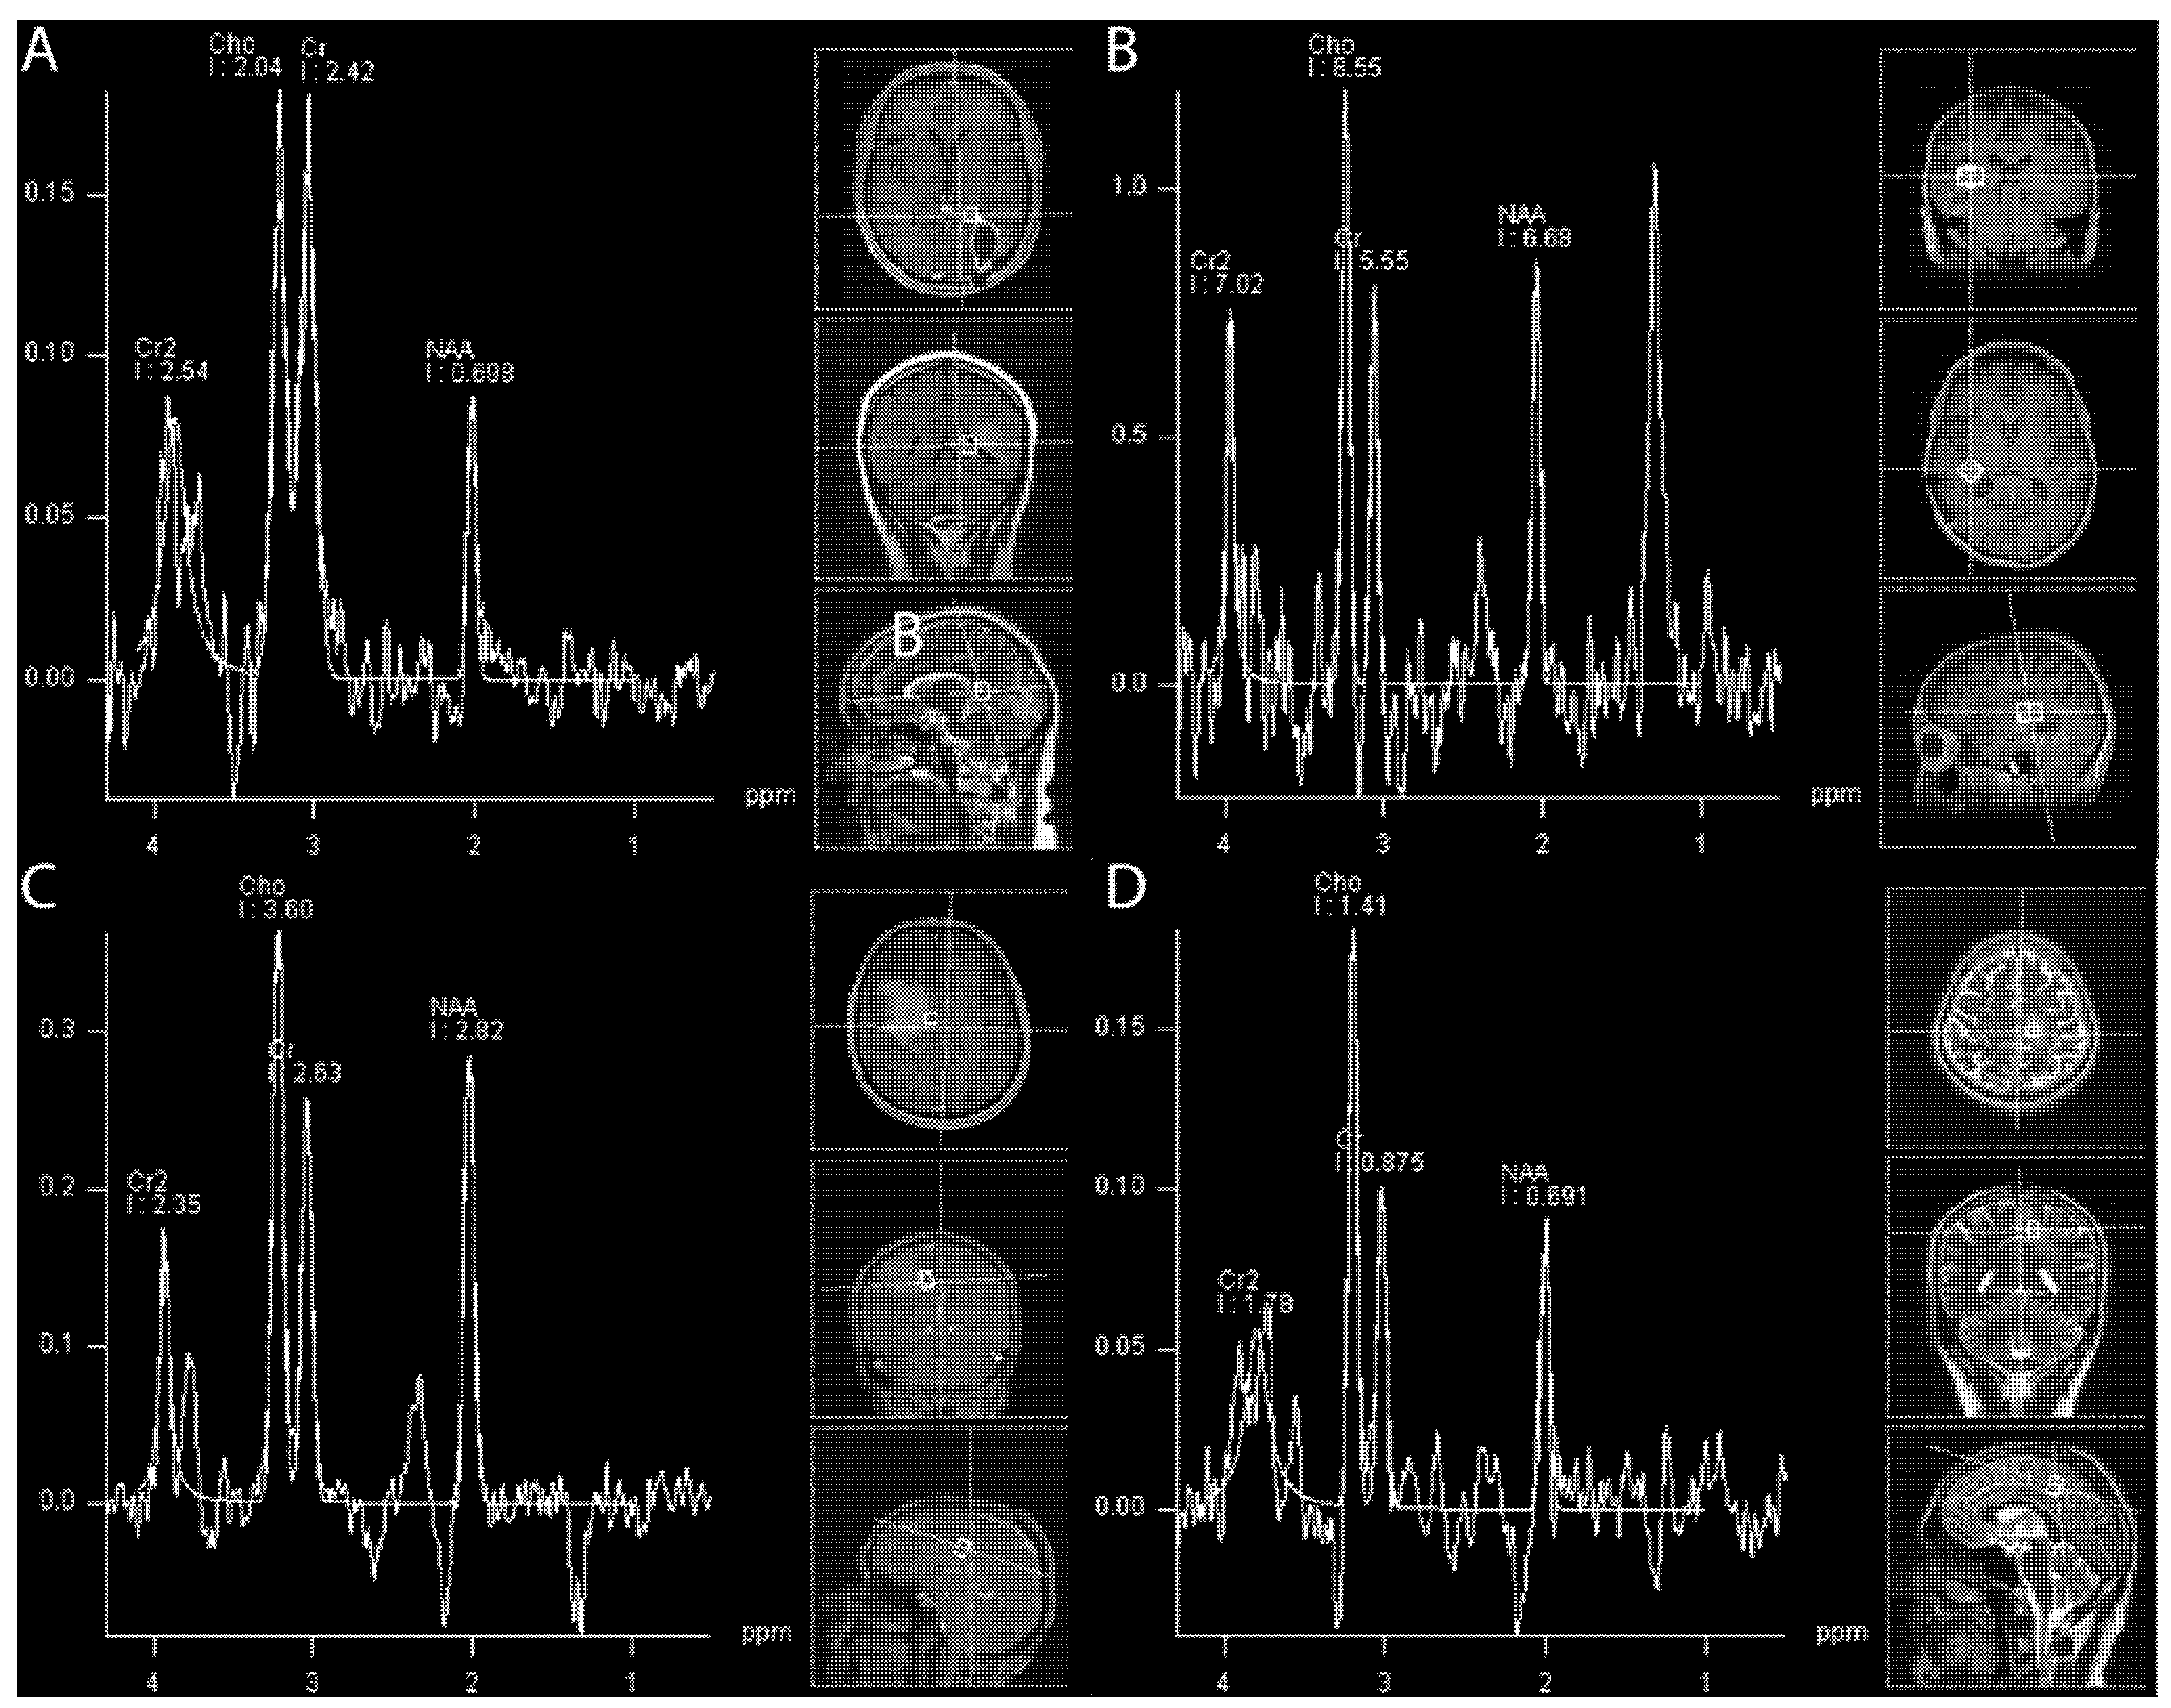

4.1.6. (1H) Magnetic Resonance Spectroscopy

- Sundgren, P.C. Mr Spectroscopy in Radiation Injury. AJNR Am. J. Neuroradiol. 2009, 30, 1469–1476. [Google Scholar] [CrossRef]

- Walecki, J.; Sokól, M.; Pieniążek, P.; Maciejewski, B.; Tarnawski, R.; Krupska, T.; Wydmański, J.; Brzeziński, J.; Grieb, P. Role of Short Te 1h-Mr Spectroscopy in Monitoring of Post-Operation Irradiated Patients. Eur. J. Radiol. 1999, 30, 154–161. [Google Scholar] [CrossRef] [PubMed]

- Amin, A.; Moustafa, H.; Ahmed, E.; El-Toukhy, M. Glioma Residual or Recurrence Versus Radiation Necrosis: Accuracy of Pentavalent Technetium-99m-Dimercaptosuccinic Acid [Tc-99m (V) Dmsa] Brain Spect Compared to Proton Magnetic Resonance Spectroscopy (1h-Mrs): Initial Results. J. Neuro-Oncol. 2012, 106, 579–587. [Google Scholar] [CrossRef] [PubMed]

- Rock, J.P.; Hearshen, D.; Scarpace, L.; Croteau, D.; Gutierrez, J.; Fisher, J.L.; Rosenblum, M.L.; Mikkelsen, T. Correlations between Magnetic Resonance Spectroscopy and Image-Guided Histopathology, with Special Attention to Radiation Necrosis. Neurosurgery 2002, 51, 912–919; discussion 919–920. [Google Scholar]

- Weybright, P.; Sundgren, P.C.; Maly, P.; Hassan, D.G.; Nan, B.; Rohrer, S.; Junck, L. Differentiation between Brain Tumor Recurrence and Radiation Injury Using Mr Spectroscopy. AJR Am. J. Roentgenol. 2005, 185, 1471–1476. [Google Scholar] [CrossRef]

- Galijasevic, M.; Steiger, R.; Mangesius, S.; Mangesius, J.; Kerschbaumer, J.; Freyschlag, C.F.; Gruber, N.; Janjic, T.; Gizewski, E.R.; Grams, A.E. Magnetic Resonance Spectroscopy in Diagnosis and Follow-up of Gliomas: State-of-the-Art. Cancers 2022, 14, 3197. [Google Scholar] [CrossRef] [PubMed]

- Grams, A.E.; Mangesius, S.; Steiger, R.; Radovic, I.; Rietzler, A.; Walchhofer, L.M.; Galijasevic, M.; Mangesius, J.; Nowosielski, M.; Freyschlag, C.F.; et al. Changes in Brain Energy and Membrane Metabolism in Glioblastoma Following Chemoradiation. Curr. Oncol. 2021, 28, 5041–5053. [Google Scholar] [CrossRef] [PubMed]